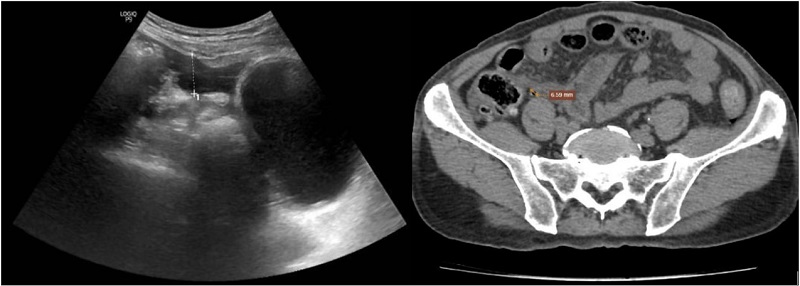

| Kết quả siêu âm (bên trái) và chụp CT (bên phải) - tiêu chuẩn chẩn đoán xác định đều cho nghi ngờ thủng tạng rỗng. |

Kết quả cho thấy nhiều bất thường. Glucose máu tăng 11,02 mmol trên lít. Ure và creatinin lần lượt 10,5 và 159,1. Mức lọc cầu thận 37 ml mỗi phút, phù hợp bệnh thận mạn giai đoạn IIIb. Hình ảnh X quang xuất hiện liềm hơi dưới cơ hoành hai bên. Siêu âm ghi nhận khí tự do trong ổ bụng. Chụp CT cho thấy nhiều dịch và khí tự do, hướng đến chẩn đoán thủng tạng rỗng vùng hành tá tràng.